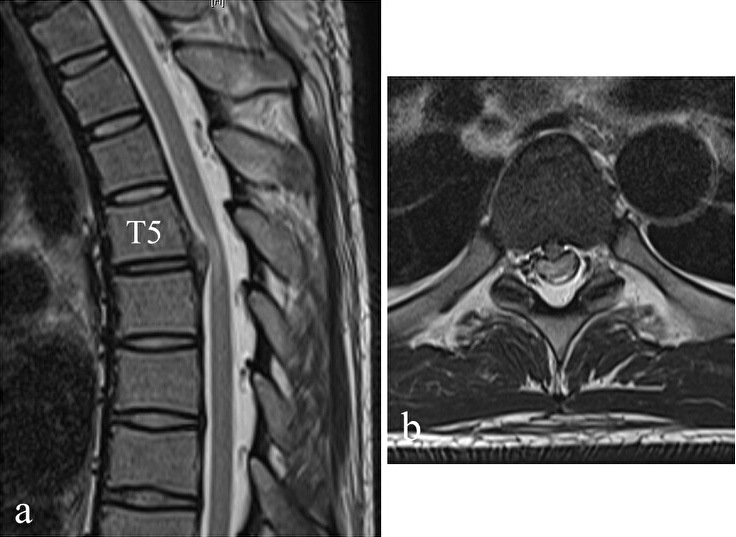

Introduction: Minimally invasive surgical treatment of myelopathy caused by central thoracic disc herniation (TDH) is challenging to carry out because reaching the herniation site is difficult and the thoracic spinal cord is fragile. In this study, using the posterior-lateral approach for central TDH with myelopathy, we present a novel procedure of transcostal microendoscopic discectomy (TCMED).

Technical note: The patient was operated in a prone position under general anesthesia. At a preoperatively determined distance from the midline, an 18-mm-long longitudinal incision was conducted, and using a 25-degree microendoscope, the operation was carried out. The endoscope was placed at an inward angle of approximately 50 degrees in the vertical direction. The ribs adjacent to the disc were identified, and the disc was exposed by resecting the ribs using a surgical high-speed drill while preserving the cortical bone of the ribs on the pleural side. The herniation was identified by drilling the ventral side of the disc and was then successfully removed. After discectomy, the dura mater expanded ventrally. Three male patients (mean age, 47.3 years) were treated, with 20 weeks of follow-up on average, 237.7-min mean operative time, and 26.7-mL mean blood loss. The average preoperative modified Japanese Orthopedic Association score was 5.2/11, which improved to 9.5/11 postoperatively, with a 75.6% average recovery rate. The 10-s step test score improved from an average of eight times preoperatively to 20 times postoperatively. No serious perioperative or postoperative complications or residual rib pain were observed.

Conclusions: The proposed TCMED approach for treating central TDH that causes myelopathy allows for safe access to the level of the posterior vertebral wall using the rib as a landmark for resecting the rib head without opening the chest. Using the angled microendoscope and curved surgical instruments, the central TDH, located ventral to the spinal canal, can then be safely and effectively resected without spinal cord retraction.